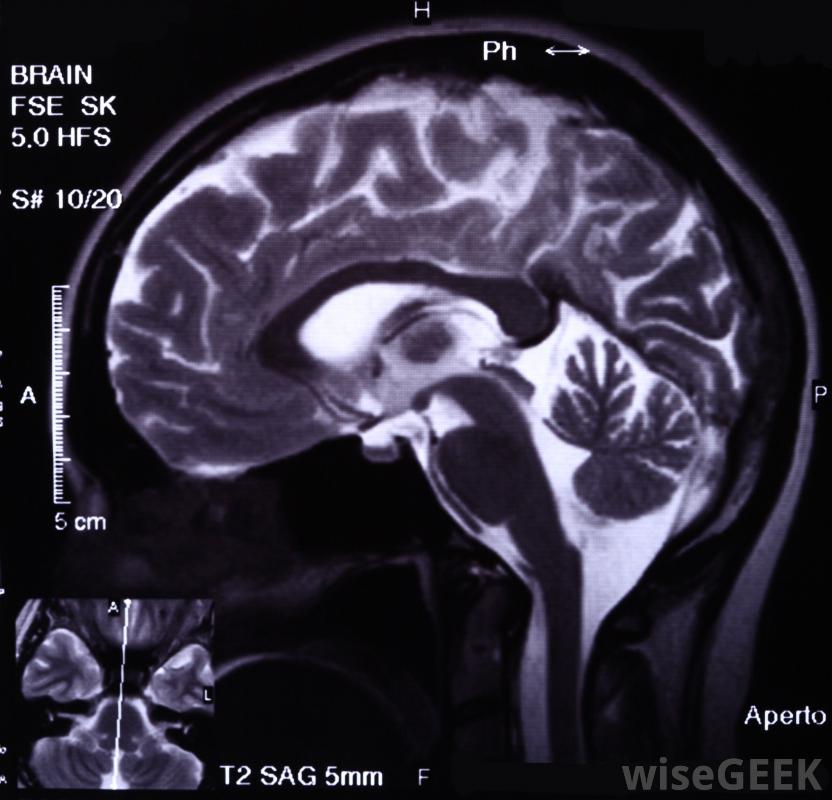

前颅窝脑膜瘤会损害人的嗅觉,颈静脉窝位于咽喉底部的颈静脉切迹处。垂体窝是蝶骨内的一个小口袋,位于中颅窝。颞窝位于颅骨的两侧,是颌骨肌肉的所在地,就在颞下窝的上方和后方。翼腭窝位于上颌后面。锁骨上窝位于锁骨上方,锁骨骨骨连接胸骨和肩部脑膜瘤通常是通过核磁共振(MRI)等脑成像来诊断的。颅窝脑膜瘤可根据其起源地进一步分类。通常根本不在颅窝,而是在许多可能的情况下,肿瘤生长到三个主要窝中的一个,可能带有额外的标记,如蝶骨翼、矢状窦旁、鞍上、岩骨、大孔、幕或斜坡脑膜瘤,以确定其确切的起源

脊髓通常被包裹在被称为脑膜的膜内,它能保护和缓冲长神经。颅窝脑膜瘤对个人健康的影响取决于肿瘤的类型——它的生长速度,主要发生在老年人的颅窝脑膜瘤几乎都是良性的,可能超过一半是无症状的,但也可能出现严重的症状,当这些肿瘤增大到足以对控制中枢神经系统、感官或重要身体功能的大脑相邻部分施加压力时脑膜瘤通常生长在大脑和脊髓周围的膜上,发生在前颅窝的脑膜瘤会损害嗅觉和视觉,或损害垂体活动性。中颅窝脑膜瘤会影响眼球运动和面部感觉,或对向大脑供血的颈内动脉施加危险的压力。后颅窝是三个颅窝中最深和最大的,因为它包含脑干和小脑,控制着大脑的一切器官和精神活动。在这个区域生长的肿瘤会导致呼吸、吞咽和说话困难,损伤听觉或味觉,或损害平衡和协调。对有症状的颅窝脑膜瘤,最有效的治疗方法是手术切除,同时切除邻近的脑组织或骨但是,与其他类型的肿瘤一样,颅窝脑膜瘤可能是复杂的,不太明确,生长在颅骨内和周围,需要更复杂的手术。无症状脑膜瘤的首选治疗方案是不去管肿瘤并监测其活动性,如果有的话。